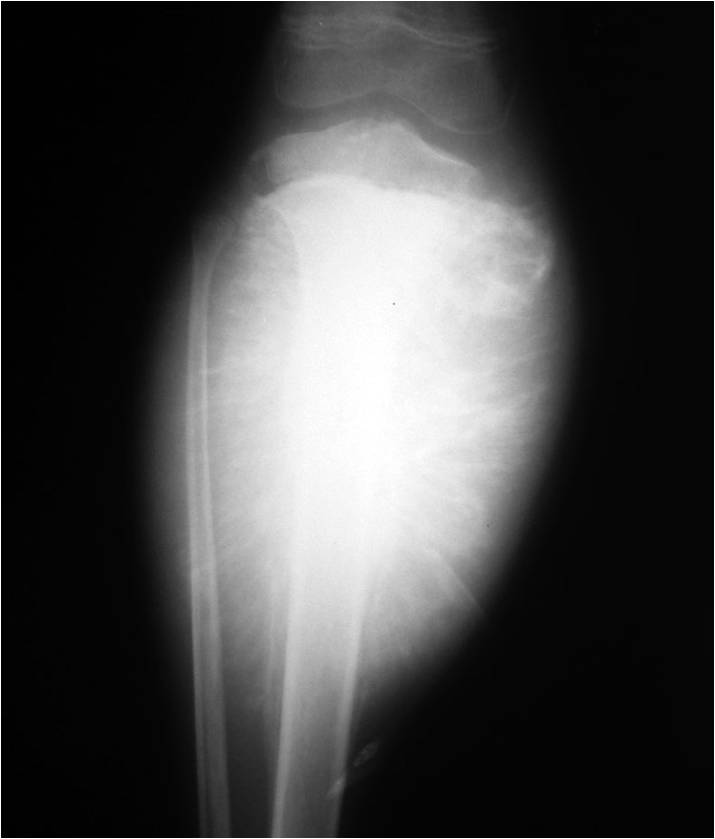

Periosteal Reaction Ddx Tumor, infection, trauma, certain drugs, and some arthritic conditions. periosteal reaction results when cortical bone reacts to one of many possible insults. Tumor, infection, trauma, certain drugs, and some arthritic conditions. — periosteal reaction. — during the healing phase, new periosteal and endosteal bone are incorporated in the cortex, resulting in a. — hyperostosis involves the exuberant production of osseous tissue and results in cortical, periosteal and/or. — periosteal reaction may be observed in the presence of a pathologic fracture. multilayered periosteal reaction, also known as a lamellated or onion skin periosteal reaction, demonstrates multiple concentric parallel layers. It can be divided in. — the most common types of periosteal response encountered with osteosarcoma are the “sunburst” type and. At mr imaging, bone marrow is. — periosteal reaction: Developmental and histologic features of normal periosteum explain some of the characteristic imaging findings seen in the setting of bone abnormalities. — the periosteum plays a key role in bone health and is a primary means by which the skeleton responds to a wide range of insults, both benign and malignant. However, it also occurs due. — periosteal reaction is a nonspecific radiographic finding that indicates new bone formation in reaction.

Periosteal Reaction AJR Periosteal Reaction Ddx How periosteum responds to stimuli (e.g., trauma, infection, metabolic process, and neoplasm) can often give clues to the etiology of the underlying stimulus. — periosteal reaction. The periosteum is a membrane that covers the majority of bone except at locations at and near cartilage. — the most common types of periosteal response encountered with osteosarcoma are the “sunburst”. Periosteal Reaction Ddx.

Periosteal Pathologic Conditions Imaging Findings and Pathophysiology Periosteal Reaction Ddx — the most common types of periosteal response encountered with osteosarcoma are the “sunburst” type and. — during the healing phase, new periosteal and endosteal bone are incorporated in the cortex, resulting in a. — periosteal reaction may be observed in the presence of a pathologic fracture. periosteal reaction results when cortical bone reacts to one. Periosteal Reaction Ddx.

Figure 3 from Malignant causes of periosteal reaction in paediatrics Periosteal Reaction Ddx How periosteum responds to stimuli (e.g., trauma, infection, metabolic process, and neoplasm) can often give clues to the etiology of the underlying stimulus. — periosteal reaction is a nonspecific radiographic finding that indicates new bone formation in reaction. It can be divided in. — physiologic periostitis describes the normal presence of smooth, bilateral, diaphyseal periosteal new bone. . Periosteal Reaction Ddx.